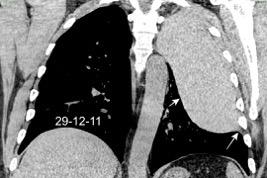

29. DERRAME PLEURAL IZQUIERDO. SÍND. DE AFECTACIÓN POSTCARDIACA

Síndrome de afectación postcardiaca (postcardiac injury)

Post infarto 1-7 % (Dressler)

Trauma cerrado Implantación marcapasos

Cirugía cardiaca. 17-31% (Post.pericardiotomía)

3707 pacientes 29 Derrames (0,78%) > de 25% del hemitórax

Todas menos 2 Izdos.

Angioplastia

By-pass coronario 21-10-03